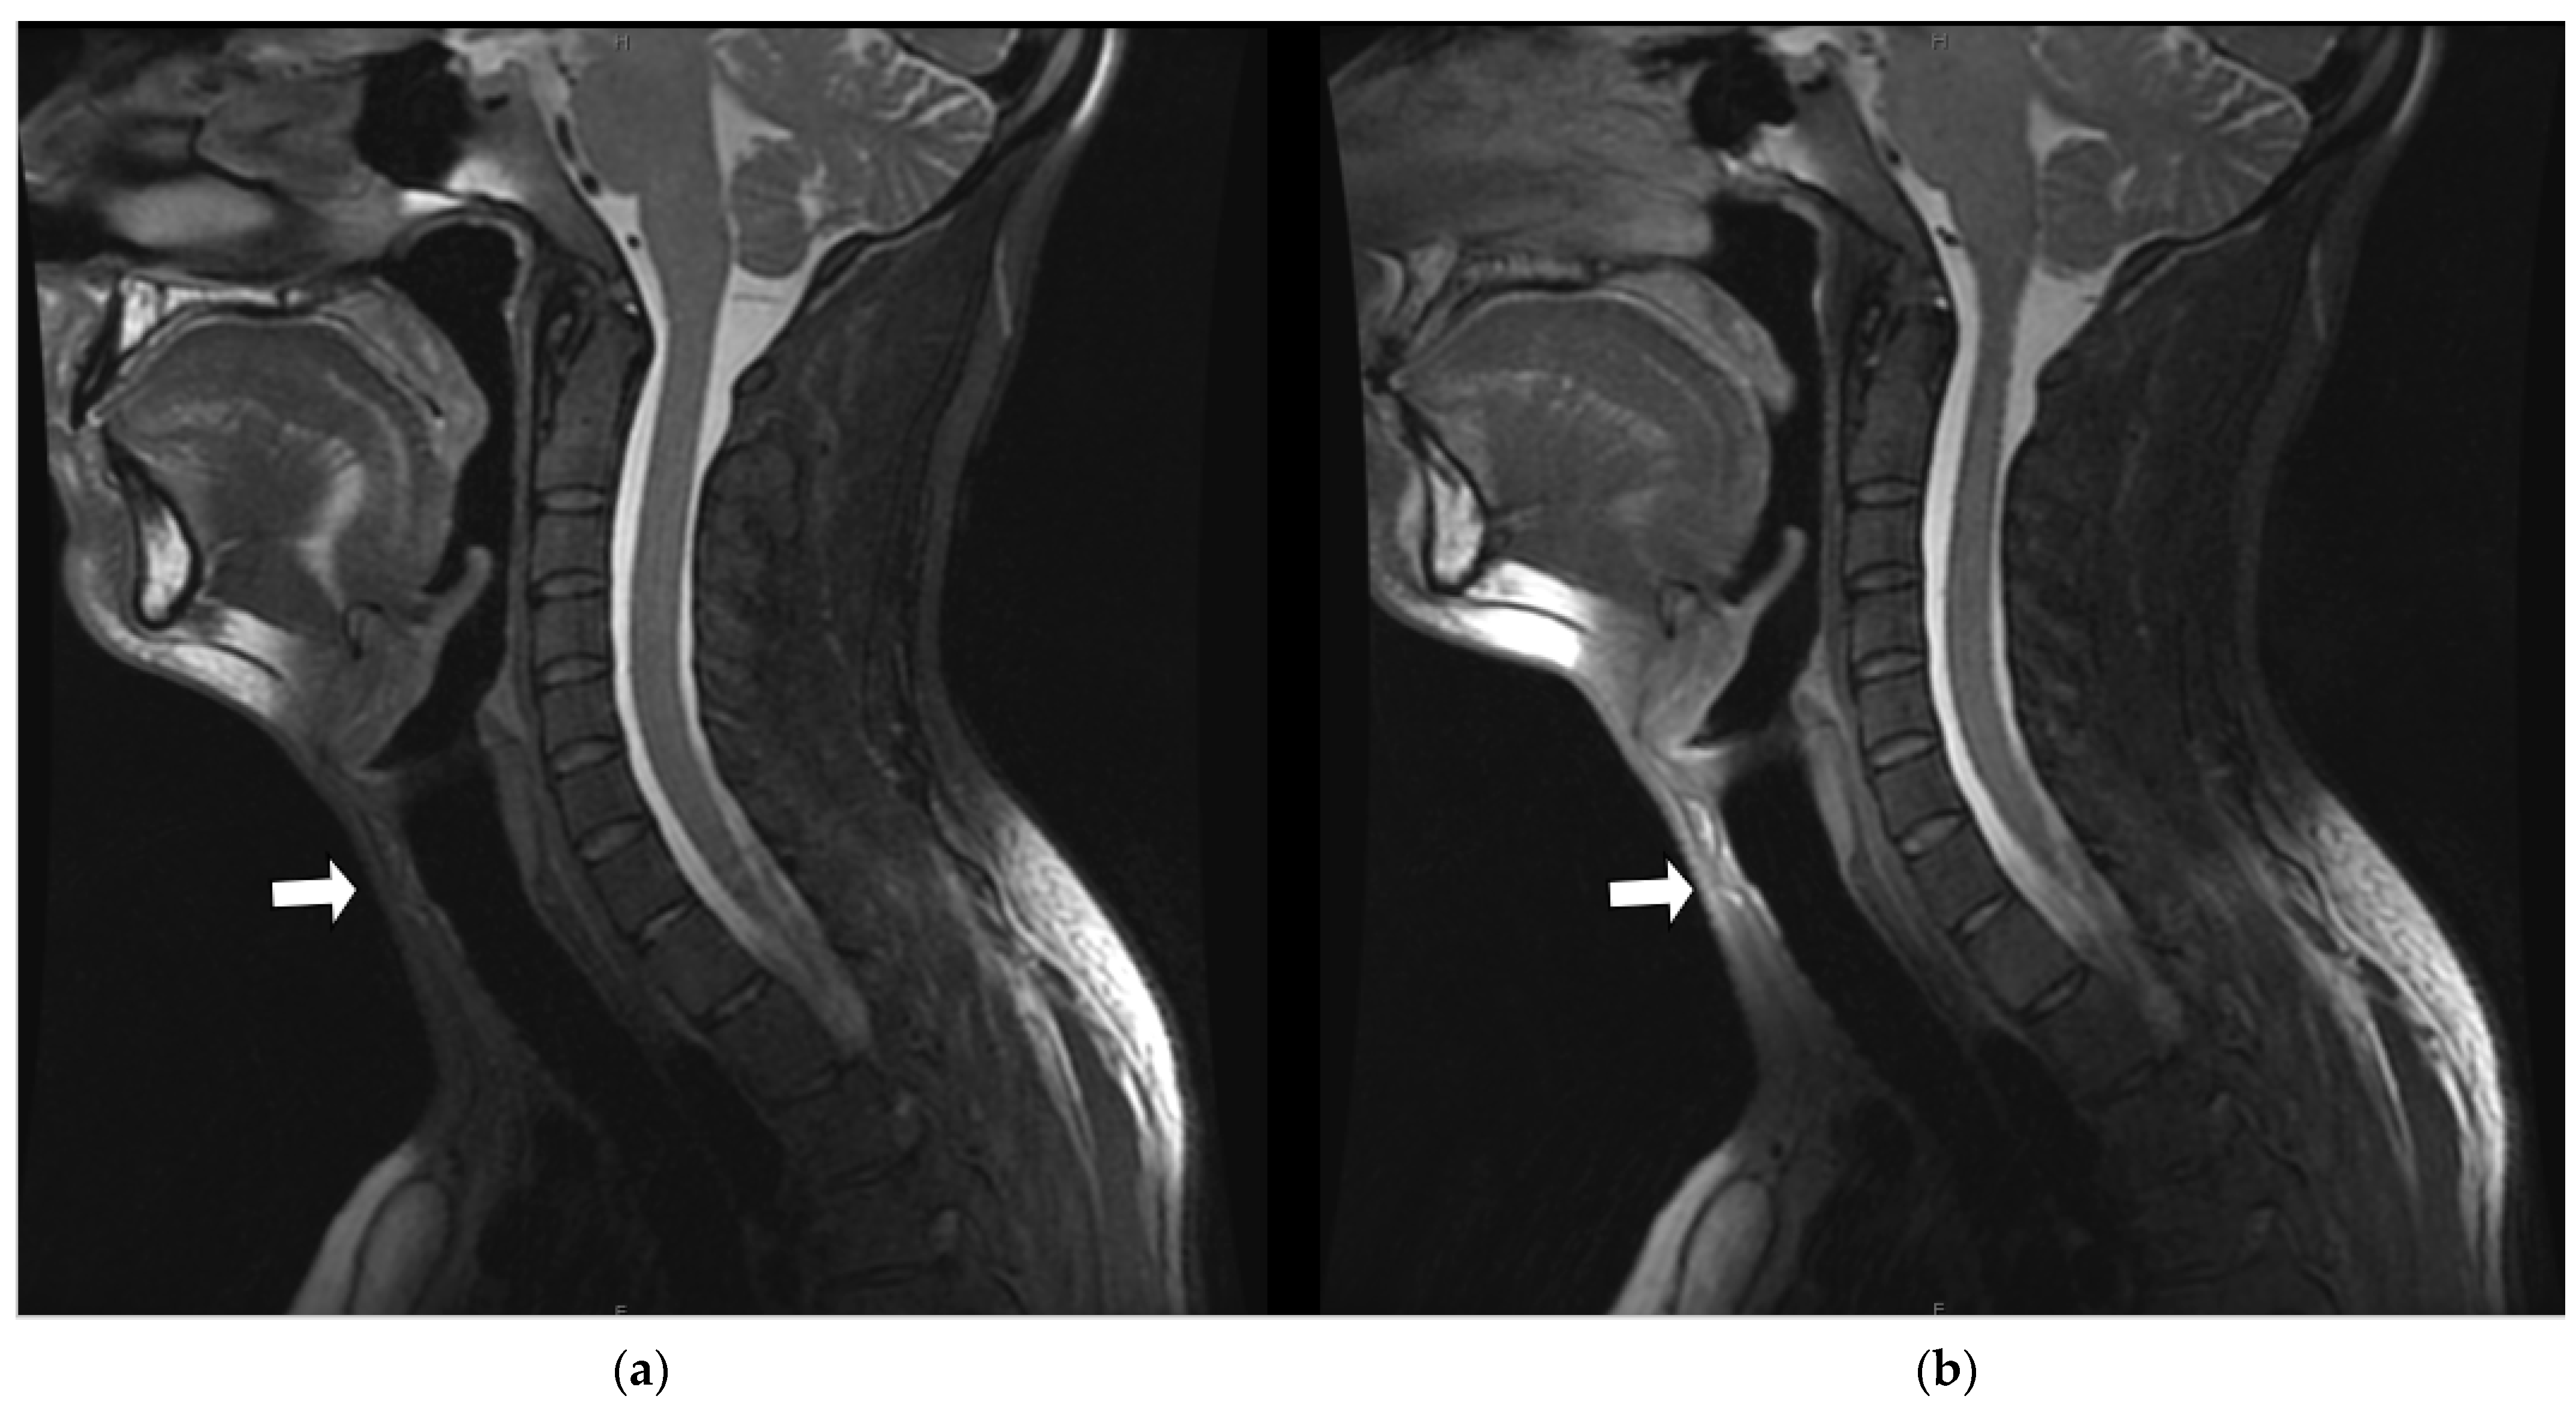

3.3.2. Artifact Enhancement

3.3.3. Coil Placement